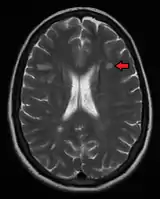

Animation showing dissemination of brain lesions in time and space as demonstrated by monthly MRI studies along a year

Multiple sclerosis as seen on MRI

Clinical data alone may be sufficient for a diagnosis of MS if an individual has had separate episodes of neurological symptoms characteristic of the disease.[53] In those who seek medical attention after only one attack, other testing is needed for the diagnosis. The most commonly used diagnostic tools are neuroimaging, analysis of cerebrospinal fluid and evoked potentials. Magnetic resonance imaging of the brain and spine may show areas of demyelination (lesions or plaques). Gadolinium can be administered intravenously as a contrast agent to highlight active plaques and, by elimination, demonstrate the existence of historical lesions not associated with symptoms at the moment of the evaluation.[53][54] Testing of cerebrospinal fluid obtained from a lumbar puncture can provide evidence of chronic inflammation in the central nervous system. The cerebrospinal fluid is tested for oligoclonal bands of IgG on electrophoresis, which are inflammation markers found in 75–85% of people with MS.[53][55] The nervous system in MS may respond less actively to stimulation of the optic nerve and sensory nerves due to demyelination of such pathways. These brain responses can be examined using visual- and sensory-evoked potentials.[56]